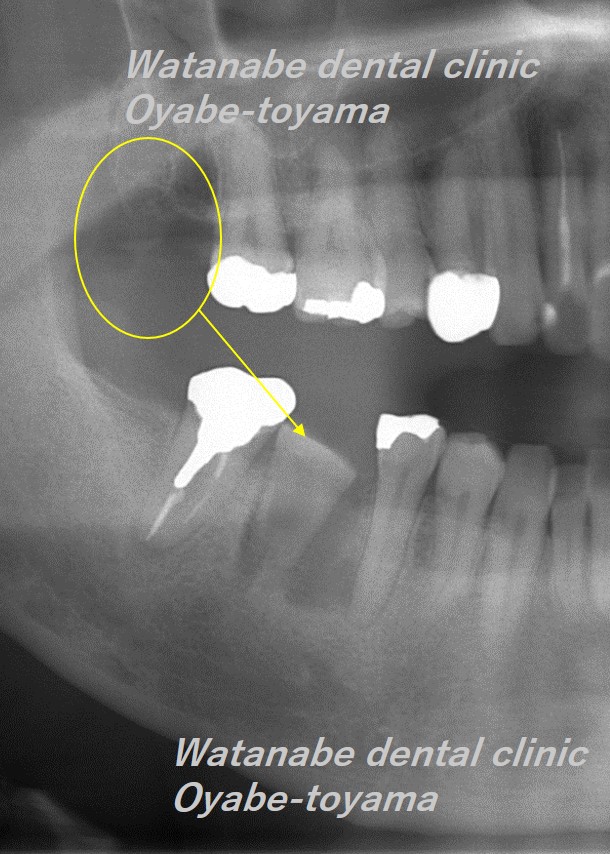

移植直後の写真です。